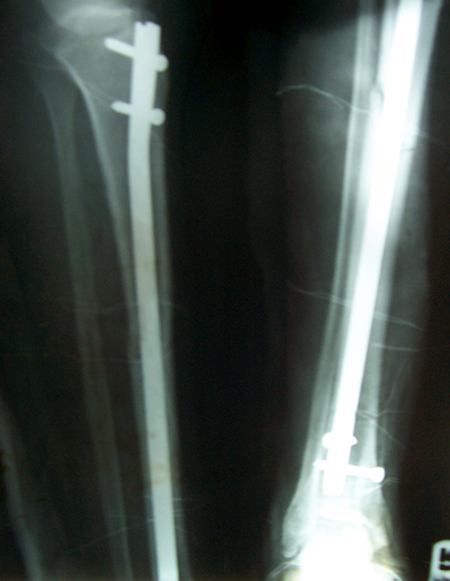

Case:8 Polytrauma

Patient having closed segmented fracture midshaft & lower 1/3 Tibia with closed fracture superior & inferior pubic rami right side with pelvis fracture following vehicular accident wastreated with intramedullary nail for fracture tibia and external fixator for fracture pelvis.

Pre-Op

Immdiate Post-op

Post-op Lateral

Ex fix with frame

Post-op 1 and half months follow-up

Post Uninon-3Months